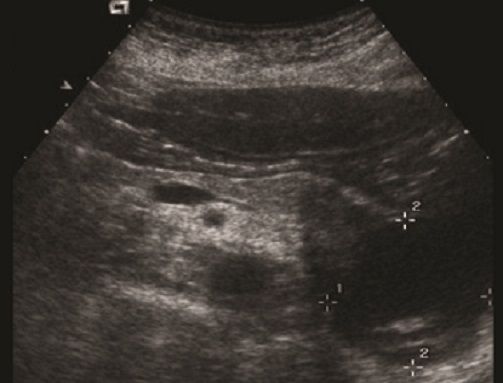

. Echographie :

Image echographique

percutanee direct de

pancreatite chronique est image de hyperechogene

heterogeneite de la

parenchyme pancreatique , sa taile peut augemente ,

normalement ou diminue sa bord est irregulier ,parfois

en presente des nodules calcification parenchymeteuse ou bien

image calcaire des calculs du canal pancreatique ce qui donne

de aspect de cone de l.ombre posterierure, en ce cas les

canal intra pancreatique sont dilates .

Les faux kyste associe peut en presente et se donne des images aechogene ou

hypoechogene intrapancreatique . Imge de ascite parfois se

en voyait